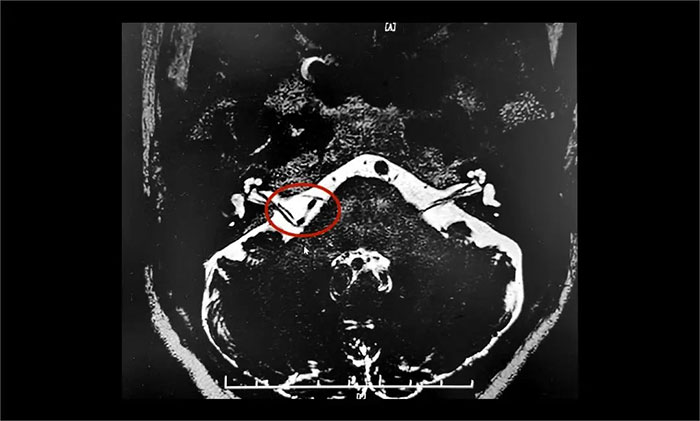

為進(jìn)一步治療,王阿姨在家人陪伴下慕名來(lái)到上海藍(lán)十字腦科醫(yī)院。入院后,楊忠旭教授團(tuán)隊(duì)認(rèn)真評(píng)估了王阿姨面肌痙攣發(fā)生的頻率、強(qiáng)度和持續(xù)時(shí)間,并完善了核磁顱神經(jīng)檢查。面神經(jīng)MRTA+增強(qiáng)顯示:右側(cè)面神經(jīng)與周圍小血管關(guān)系密切。

▲ 右側(cè)面神經(jīng)與周圍小血管關(guān)系密切

楊忠旭教授認(rèn)為,患者藥物治療效果不佳,癥狀反復(fù)發(fā)作,已影響日常生活,手術(shù)指征明確,未見明顯手術(shù)禁忌癥。在告知患者及家屬手術(shù)風(fēng)險(xiǎn),取得家屬同意后,楊忠旭教授團(tuán)隊(duì)為患者實(shí)施了神經(jīng)電生理監(jiān)測(cè)下微血管減壓術(shù)。